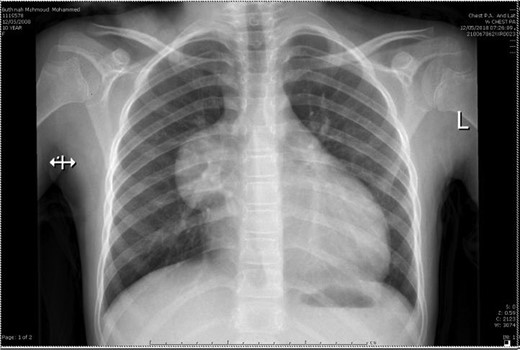

A 10-year-old female patient was well prior to an evaluation for chest pain of two weeks duration, at which an anterior mediastinal mass, was noted on chest radiograph. Chest X-ray (Fig. 1) showed a well-defined homogenous opacity in the right upper and mid zones extending from mediastinum and obliterating the hilar shadow. Transthoracic echocardiography revealed a pericardial effusion. Chest CT (Fig. 2) revealed a well-defined tumor mass involving the anterior mediastinum adjacent to the heart measuring 6 × 4 cm. Mild amount of pericardial fluid noted.